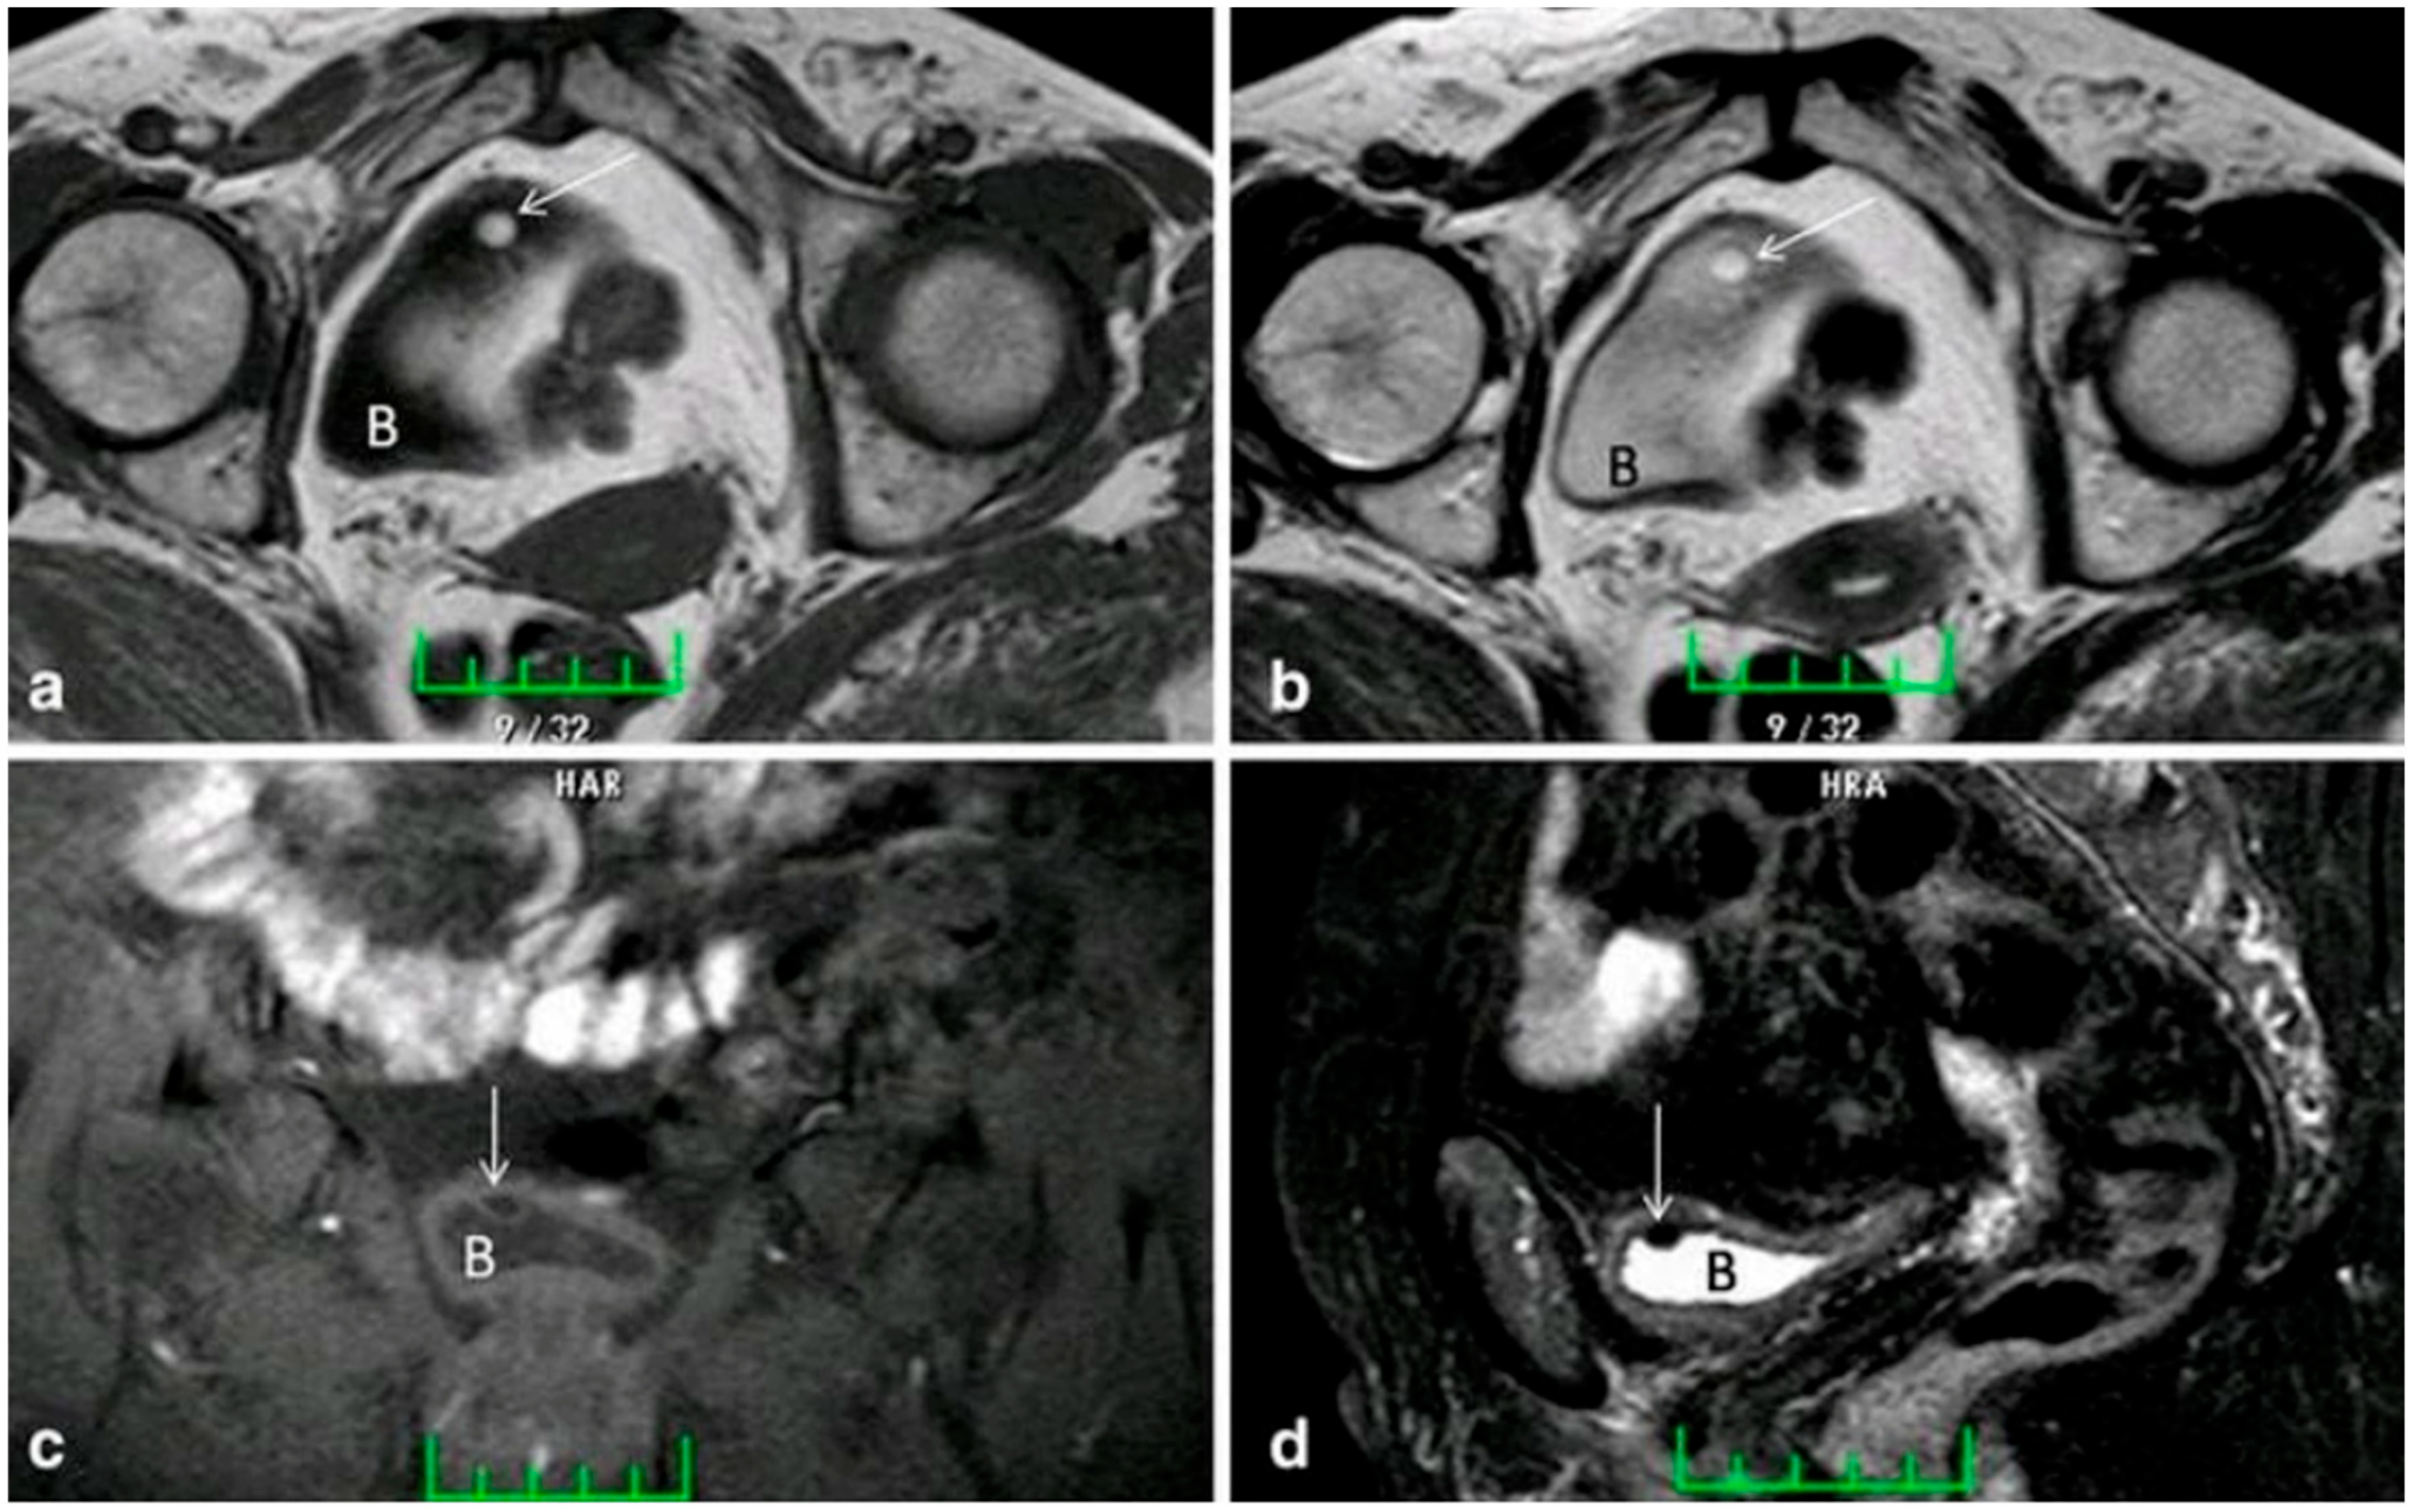

| MRI | Common Features: Homogenous, endophytic bladder nodule with smooth margins. | -Chung A.D et al. reported that the visibility of lipoma can be diminished by the hyperintense signal of the nearby urine. Noting the chemical shift artifact in the frequency encode direction may help in the diagnosis [16]. -Brown C et al. reported lipoma associated with UT, a relatively rarer presentation for lipoma; the patient had a cystoscopy followed by a pelvic MRI, which revealed the lesion [15]. -An interesting case reported by Ukita S et al. revealed a lipoma in the R retropelvic cavity arising from the bladder, measuring about 15 cm as seen on T1- and T2-weighted MRI. The positions of the broad ligament, uterine ligament, and iliac arteries helped determine the location of the lesion prior to surgical intervention [16]. |

| T1-Weighted Sequences: Hyperintense signal due to fat content (Figure 6a) [18]. | ||

| T2-Weighted Fast Spin Echo (FSE) Sequences: Hyperintense signal due to J coupling effect (Figure 6b) [18]. | ||

| Fat-Suppressed Imaging: Hypointense signal using techniques like chemical fat suppression, inversion recovery, and Dixon methods (Figure 6c,d) [18]. | ||